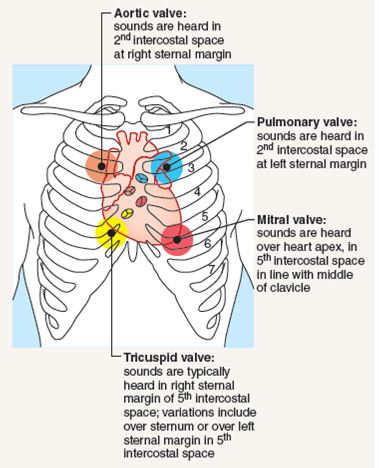

Auscultating Heart Soundsin The Following Procedure Yo

Auscultating Heart Soundsin The Following Procedure Yo

Surface Markings Of The Cardiac Valves And Auscultatory

Surface Markings Of The Cardiac Valves And Auscultatory